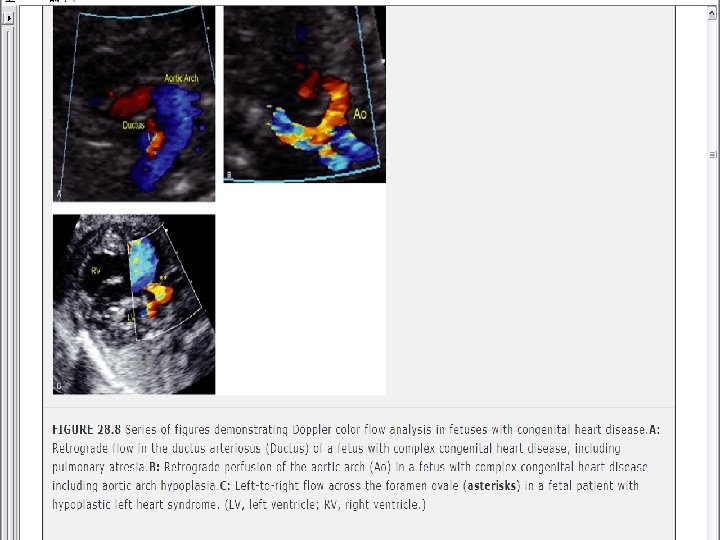

screening fetal echocardiogram • For patients with a previous child or 1 stdegree relative with CHD, • For patients who are at higher risk of having a child with cardiac disease insulin-dependent diabetics, patients with exposure to teratogenic drugs during early pregnancy), any fetus in which a chromosomal abnormality is suspected or confirmed.